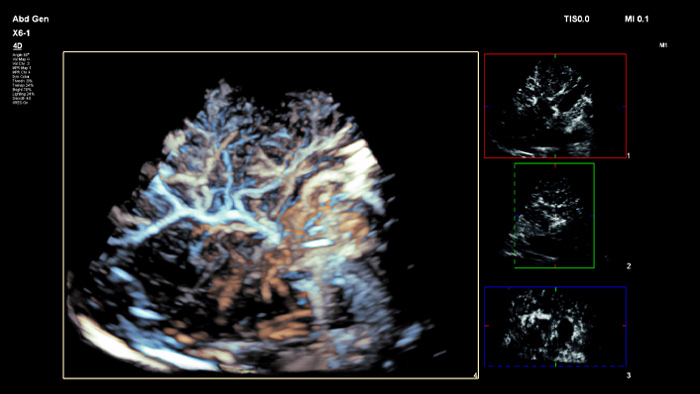

Tome decisiones fiables incluso en casos diagnósticos complejos gracias a las funciones de navegación guiada por aguja y fusión de imágenes de Philips. El flujo de trabajo agilizado permite a los médicos conseguir una fusión rápida y efectiva de imágenes TC/RM/PET mediante ecografía en tiempo real, mientras que la navegación guiada por aguja permite guiar la biopsia en lesiones pequeñas o de difícil acceso.2.

Mediante el uso de la función de contorno tumoral, los usuarios pueden planificar y dirigir las lesiones con una herramienta semiautomatizada que ayuda a trazar un contorno 3D alrededor de una estructura de interés, lo que puede mejorar la guía del procedimiento en casos difíciles en los que la lesión no se pueda visualizar fácilmente.